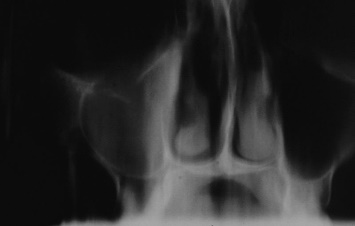

Zlomenina mediální stěny očnice

Mezi příznaky zlomeniny mediální stěny očnice patří:

- epistaxe

- podkožní emfyzém

- enoftamus

- horizontální diplopie